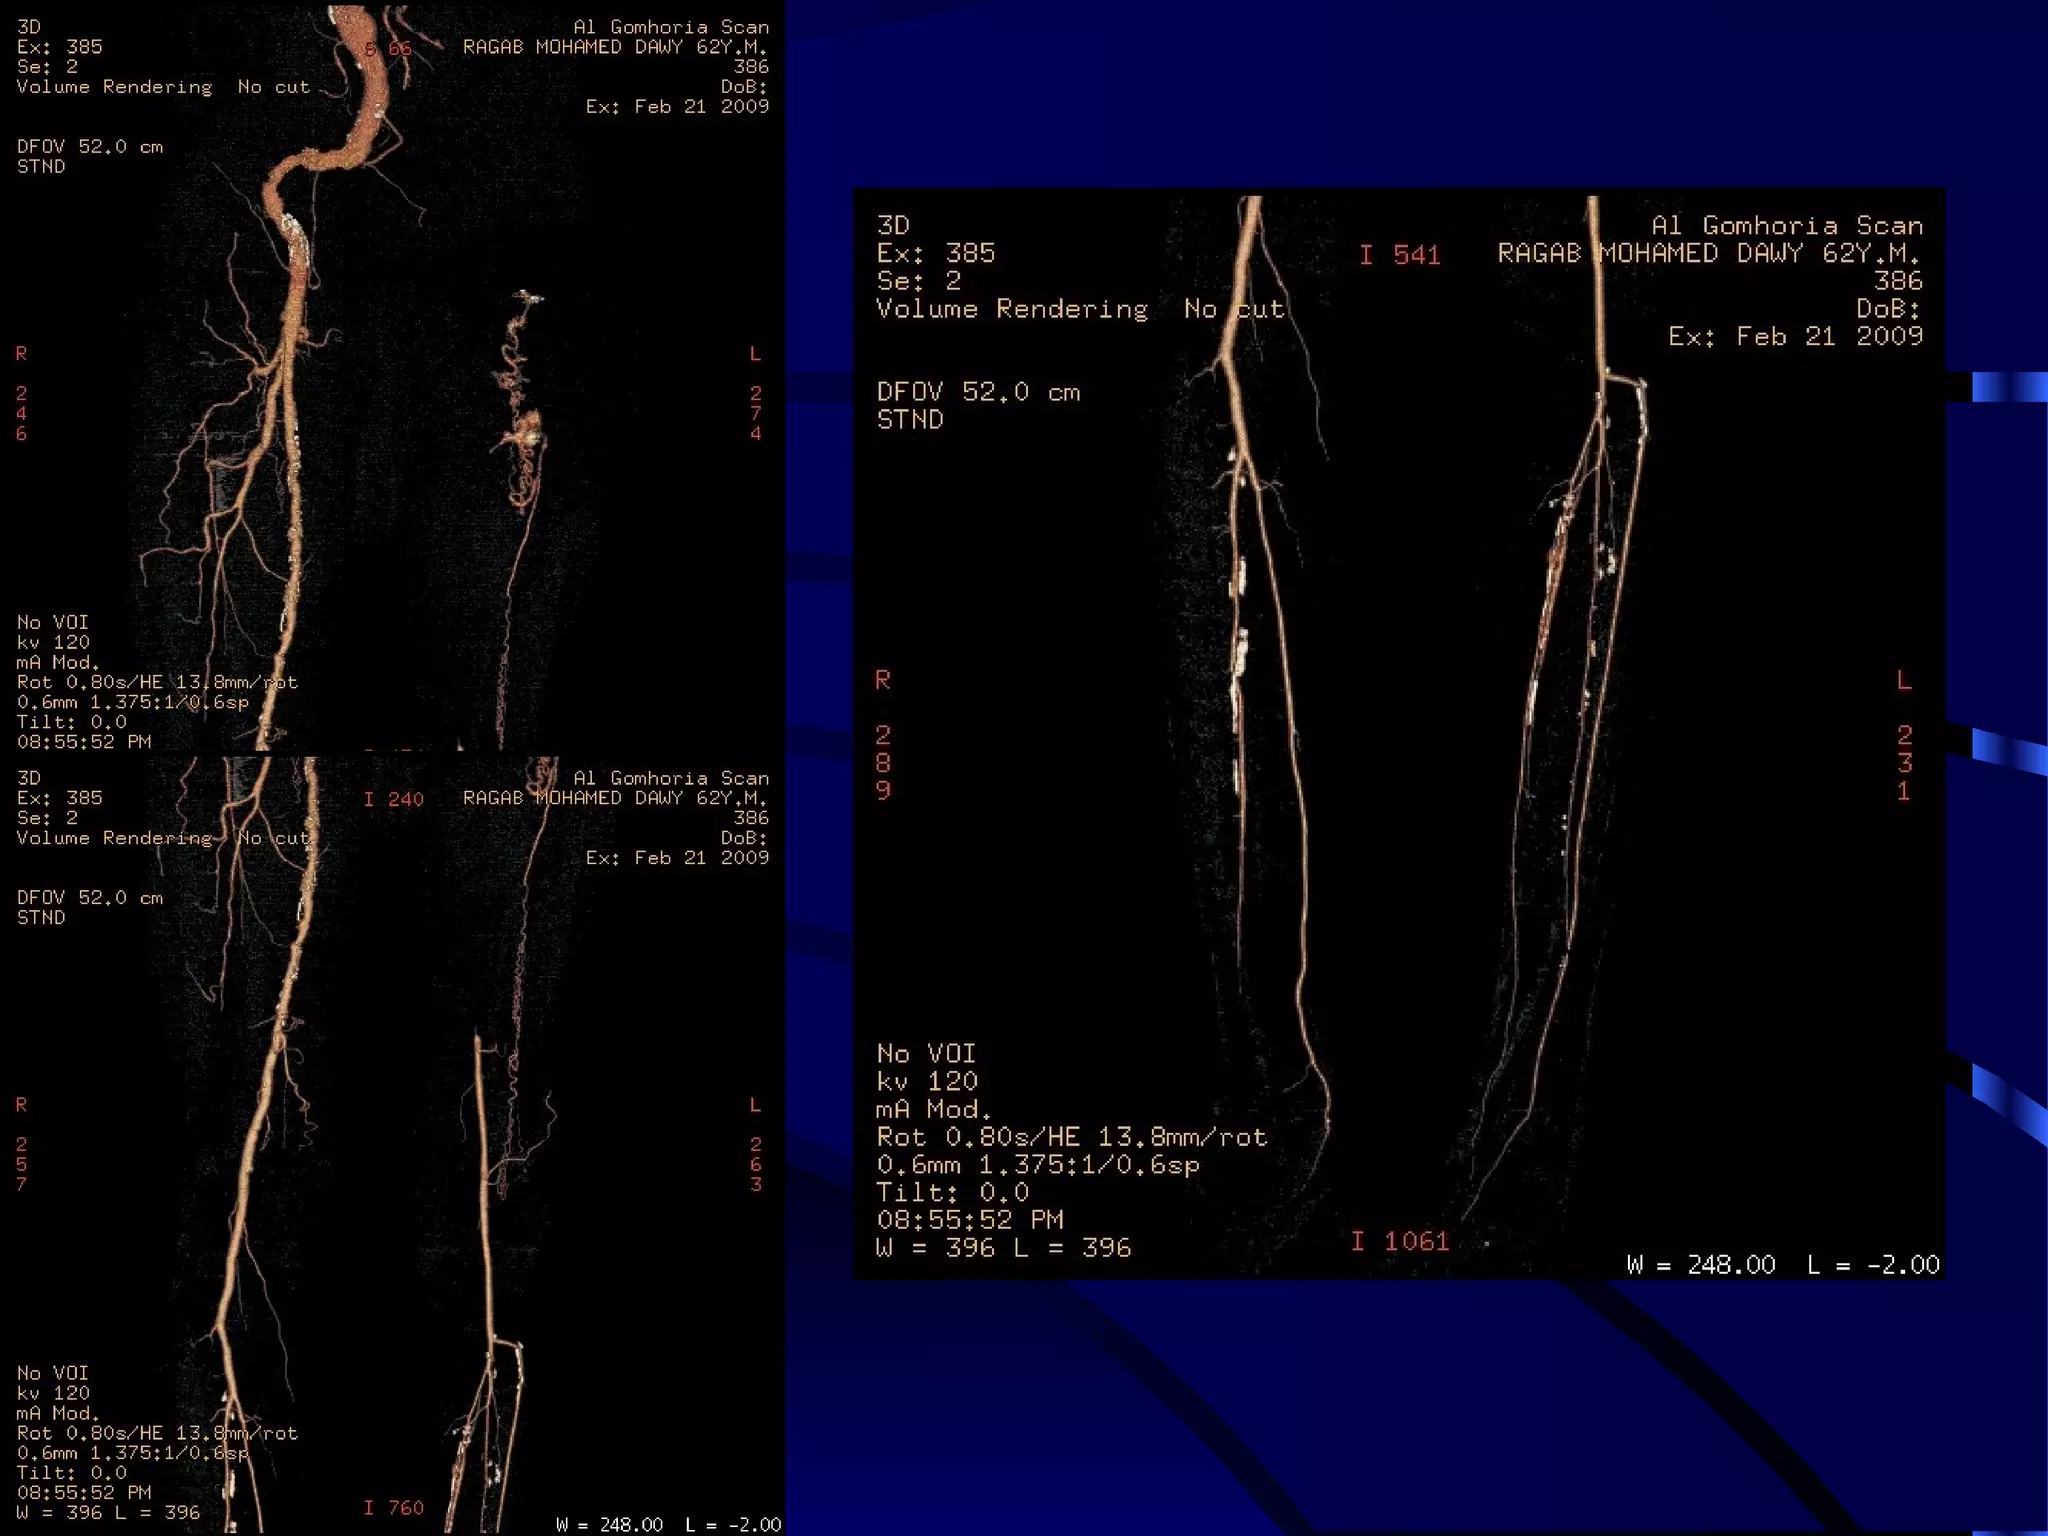

LOWER LIMB

ARTERIOGRAPHY